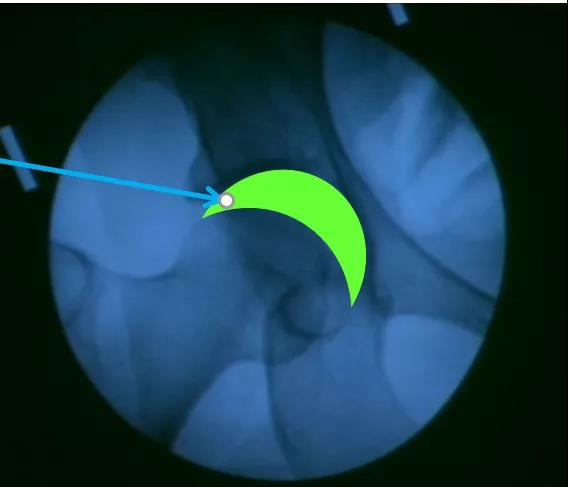

髋关节穿刺注射部位理想进针区域:牵引下C臂机透视关节间隙“新月征”

高难度红色区域:无牵引、无C臂机容易进针安全区域:绿色框内